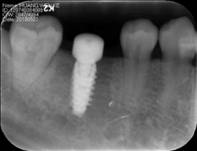

种植治疗是一种以植入骨组织内的下部结构(种植体)为基础来支持/固位上部修复体的缺失牙修复方式,是治疗牙齿缺失的一种较新的、成熟的临床技术。医生需要根据理想的缺失牙修复方案所要求的植体分布和三维方向、结合患者口腔局部和全身条件,设计制定合理的种植外科方案后,经手术方法将种植体植入组织内(通常是上下颌)、并获得骨组织牢固的固位支持,最后通过特殊的装置和方式连接支持上部的修复体。目前常用的种植体材料主要是钛、上部暴露于口腔内的修复体材料趋同于天然牙修复材料。

修复导向种植治疗方法的主要优点是主要依靠种植体的支持,恢复缺牙区的软硬组织形态、实现预期的功能与美学目标,这种方式更加符合口腔生物力学的要求,从而有利于获得更为长期的修复成功率。

(图片由修复科韩彦峰医生提供)